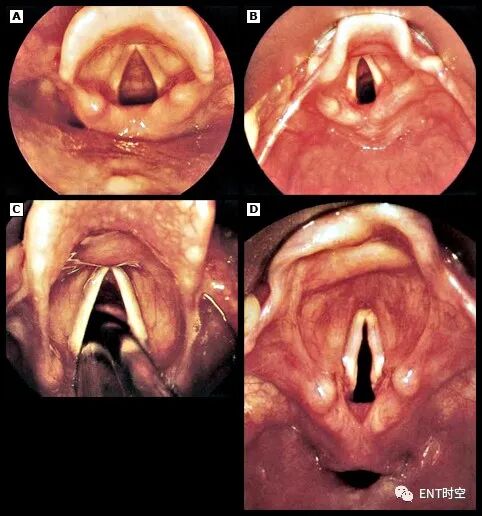

喉部外观与视频喉镜:使用视频喉镜获得的几张喉部照片:(A)成人气道的插管前视图;(B) 儿科气道插管前视图;(C) 在声带之间通过的气管导管;(D) 喉部和下咽部的视图(注意喉部入口下方的水平空间,即食道)。